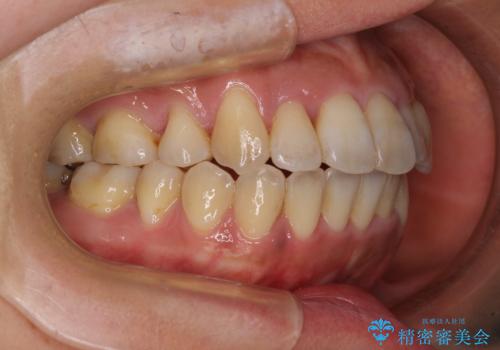

狭い上顎骨を拡大 著しい叢生を抜歯矯正で改善

治療途中、長期間海外旅行をされたり、帰国後には遠方へ転居されたりと、治療期間が伸びましたが、2年強で治療を終えることができました。